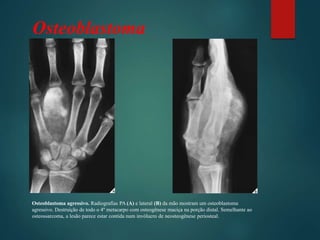

Osteoblastoma agressivo. Radiografias PA (A) e lateral (B) da mão mostram um osteoblastoma

agressivo. Destruição de todo o 4º metacarpo com osteogênese maciça na porção distal. Semelhante ao

osteossarcoma, a lesão parece estar contida num invólucro de neosteogênese periosteal.